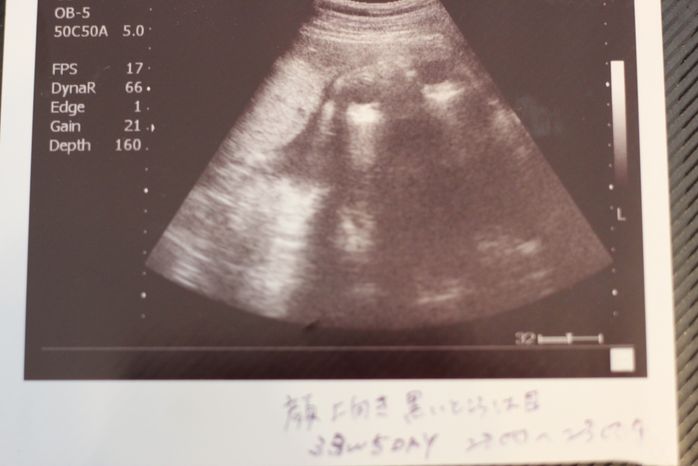

妊娠33週目のエコー写真

「顔上向き、黒いところは目。2200g~2300g」と記してあります。右上にある黒い丸2つが目でその間に鼻がうつっています。口を開けているところ?このころは、おなかが大きくなり自分で足の爪を切ることが難しかったので、看護師さんにお願いしていました。